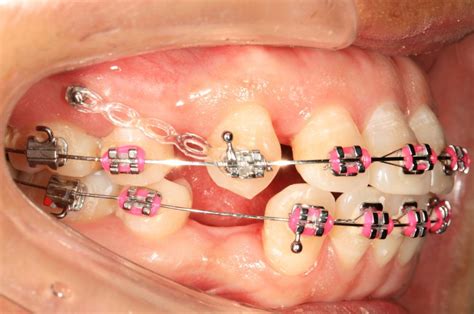

Las opciones de tratamiento con cirugía ortognática o extracciones dentales fueron descartadas ya que este caso se puede solucionar correctamente con microtornillos de anclaje. Para intruir los molares superiores y distalar ligeramente la arcada inferior, para mejorar el engranaje de la boca, se utilizan 4 microtornillos colocados detrás de cada muela (2 arriba y 2 abajo). Este tipo de tratamientos de ortodoncia pertenece a un grupo de tratamientos que utilizan el anclaje distal con microtornillos para mover los dientes hacia donde nos convenga más.

En este caso de clase II usamos anclaje distal para mover hacia atrás los molares superiores y en este caso de clase II con mordida abierta tratado con ortodoncia lingual usamos el anclaje distal con microtornillos para mover los molares superiores hacia arriba y hacia atrás lo que ayudo a cerrar la mordida abierta.